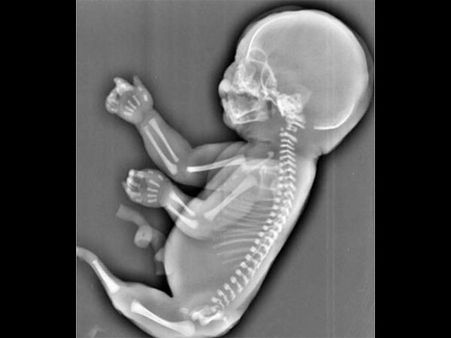

Her Foetus Looked Like A Mermaid!

This is one of the rarest cases where an ultrasound of the foetus revealed something shocking, as the foetus looked like a mermaid! Check out what the mum did…

The ultrasound revealed that the foetus had a tail-like protrusion instead of legs. Doctors informed her that this condition is known as the "mermaid syndrome or sirenomelia". It is a rare condition, but it is existent!

She was apparently heart-broken that her baby had the mermaid syndrome and the baby was said to be completely deformed and it had a tail in place of legs.

Mermaid syndrome is said to be a very rare condition, in which the baby hardly survives for a short span; and if it is born alive, it survives only for a few hours and not more than that!

The causes of this kind of a birth defect are still not known, but this rare disorder affects one in every 100,000 babies!

According to reports, there are only two survivors of this rare syndrome in the world. Milagros Cerron and Shiloh Pepin are the two lucky girls who survived this condition.